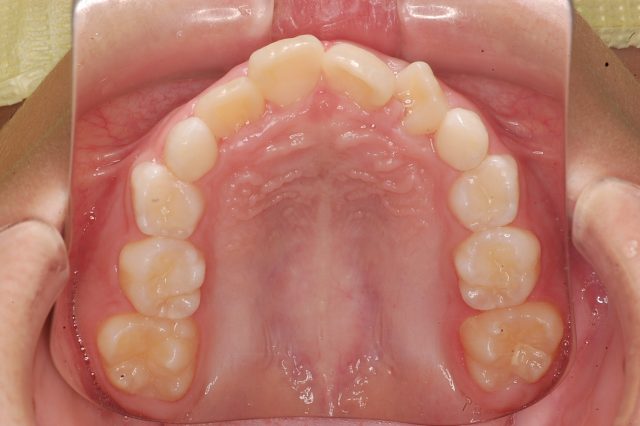

8歳男の子インビザラインファースト:永久歯スペース不足を解消

| 年齢・性別・主訴 | 8歳男の子 永久歯が並ぶスペースが足りない |

他のAfter